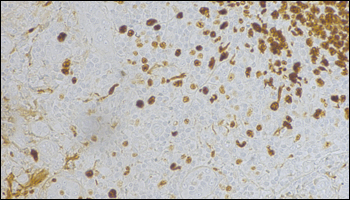

Click here to view the full-resolution image.

Ki-67で染色した試料を倍率20倍で取得した画像。カラーカメラCS505CUが免疫組織化学(IHC)への応用に適していることを示しています。